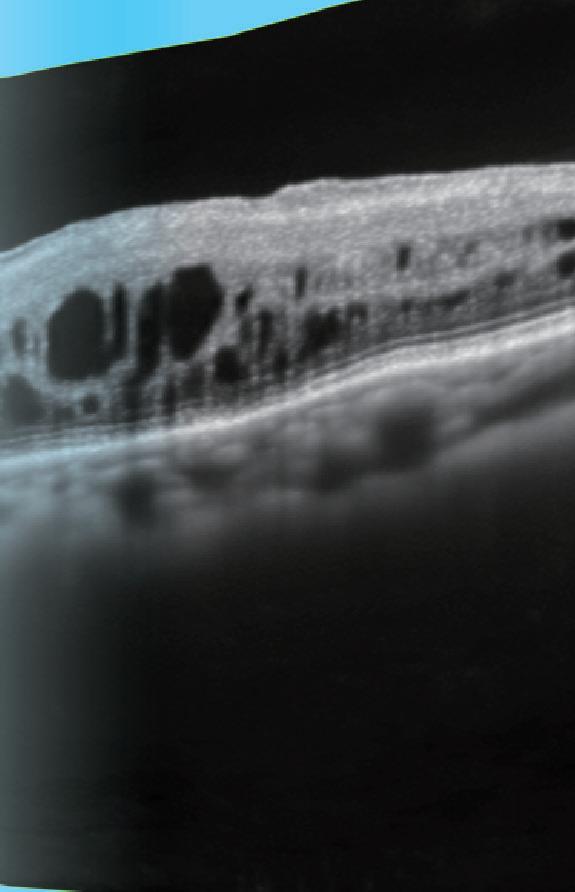

When he was brought to our clinic in Lviv, one eye was completely destroyed, and the other had a subconjunctival rupture of the sclera, complete vitreous haemorrhage, and total retinal detachment. Visual acuity of this eye was an incorrect light perception.

The operation lasted more than five hours. At first, it was impossible to distinguish between the blood, the membranes, and the retina. The operation ended with a 360-degree circumferential and radial retinotomy, and an endotamponade with silicone oil. The retina was grey, and I had no hope for him to recover the slightest sight ability. After ten days of recovery, the BCVA was 0.01, and I am happy I could give him back at least some sight.

The fourth case: Military, not young anymore, a strong man. The guy was silent, but I could feel his despair and hopelessness. He had had surgery before coming to Lviv.

His crushing despondency painfully hit me as my own. He was wounded and covered with dirt. One eye was destroyed—very badly injured and with endophthalmitis. The second eye had sutured corneal wound, swollen cornea, hyphaema, iris coloboma, aphakia, and silicone oil tamponade. The fundus could not be ophthalmoscopically examined. Ultrasound examination was unclear. Incorrect light perception. I understood something was wrong inside, and I waited for the cornea to become more transparent before an operation. I removed the epithelium and the silicone oil. There was almost no retina on the temporal side, silicone under the retina. The retina was shortened and shrunken. I straightened it in the best way I could, but there was no central part of the retina. I felt powerless…

Retinal Considerations for Cataract Surgery

Don’t lose sight of retinal disease when visualising outcomes.

By Dr Soosan Jacob MS, FRCS, DNBFar from the realms of the cataract surgeon but still crucial to planning and outcomes, appropriate knowledge about retinal diseases is important when contemplating cataract surgery. The goal is to provide a good visual outcome without exacerbating underlying retinal disease or creating any new problems with the retina.

EPIRETINAL MEMBRANE (ERM) AND VITREOMACULAR TRACTION

Studies have shown roughly 7–8% risk of CME after cataract surgery in eyes with epiretinal membrane (ERM). Vitreous liquefaction and forward movement of the vitreous are known to increase the risk of CME. Epiretinal membranes are more common in diabetics, and these further increase the risk of CME. In addition, the ERM may progress more quickly after cataract surgery necessitating surgery. The decision to combine phacoemulsification with ERM peeling depends on the visual significance of the ERM. Amsler grid distortion and disruption of the outer retinal anatomy on OCT are indications for combined surgery.

RETINAL COMPLICATIONS OF CATARACT SURGERY

Cataract surgery can also induce retinal complications. These range from globe perforation during the peri-ocular block to posterior capsular rent (PCR) with ensuing vitreous loss, nucleus or IOL drop, and/or retained lens fragments. Several factors may increase the risk for CME, vitreous base traction, retinal tears (including giant tears), and retinal detachment. These include chamber fluctuations, PCR or other complications, postoperative inflammation, complex or comorbid eyes, and certain inappropriate surgical manoeuvres. Pseudophakic rhegmatogenous retinal detachment occurs in about 1% of cases, with 50% occurring within the first year of surgery.